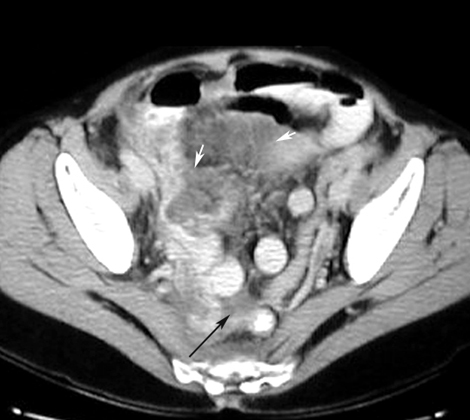

GI and Abdomen Case 4:  Appendicitis / Abscess

CT: Highly accurate

Signs: